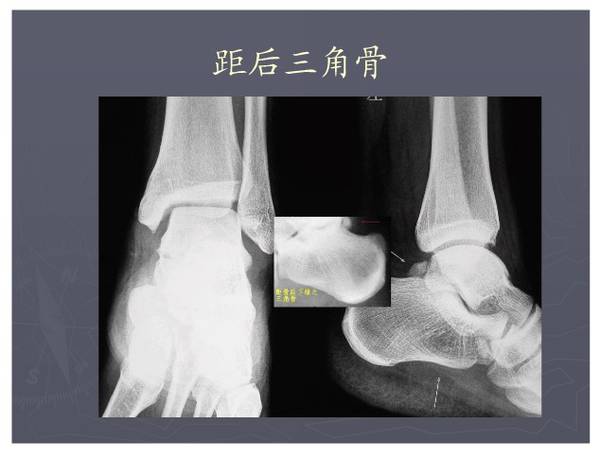

常见异常副骨或籽骨